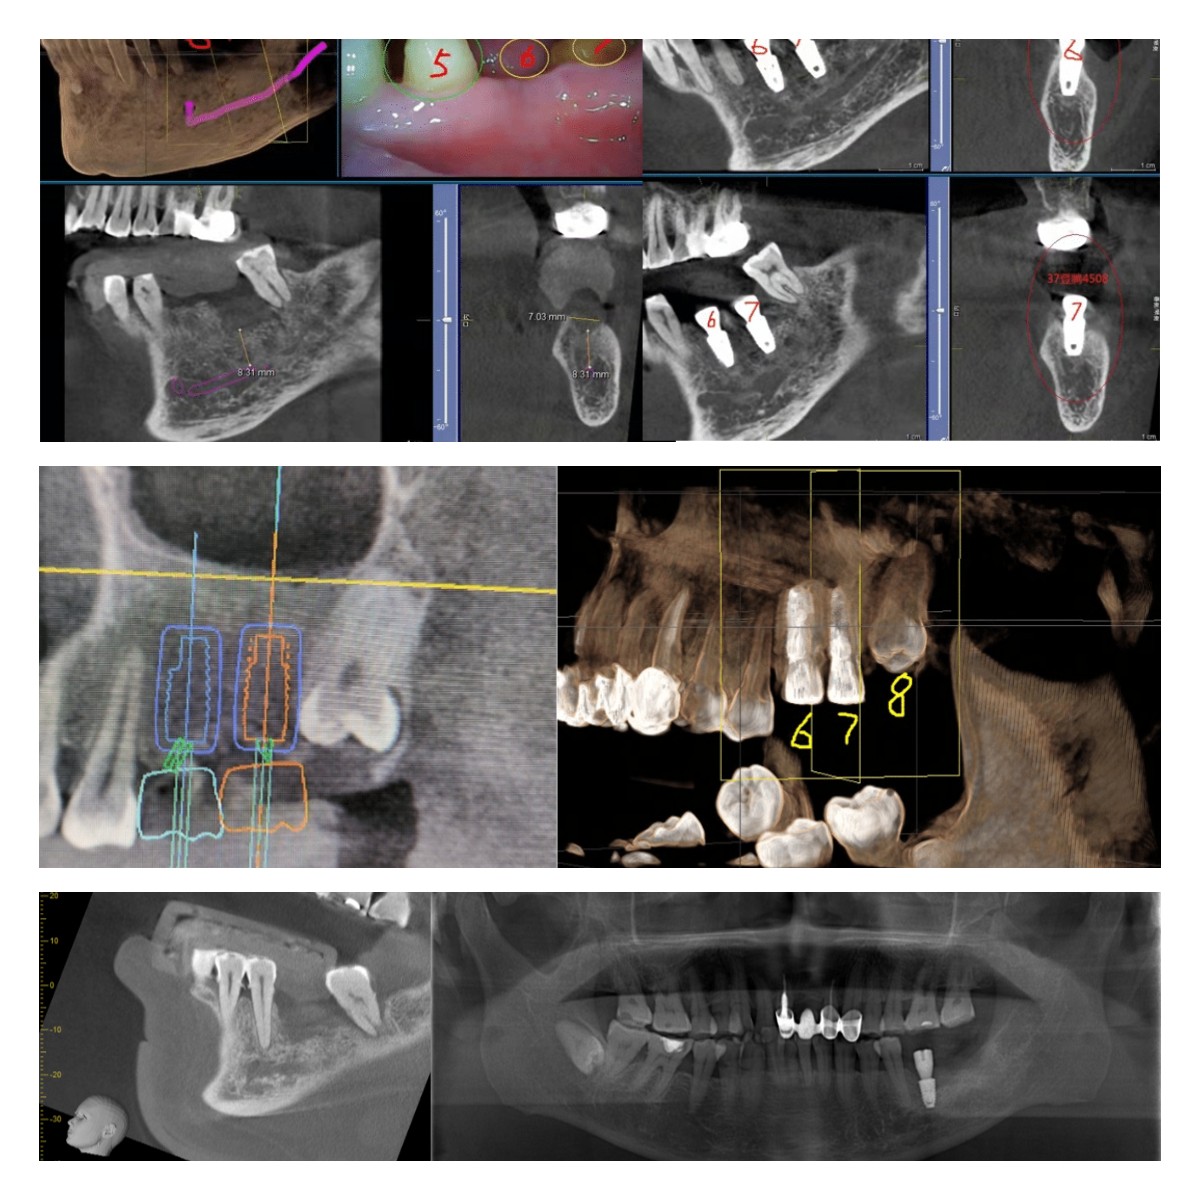

部分病例展示:

在這里,小編為大家一一解答~1、使用動(dòng)態(tài)導(dǎo)航進(jìn)行種植,即刻種植、即刻修復(fù),減少就診時(shí)間;2、傳統(tǒng)種植只能夠憑借經(jīng)驗(yàn)進(jìn)行種植,無(wú)法在手術(shù)過(guò)程中看見(jiàn)植入植體的位點(diǎn)、角度和深度,而動(dòng)態(tài)導(dǎo)航是可視化種植,按照設(shè)計(jì)好的種植方案,進(jìn)行手術(shù)并實(shí)時(shí)監(jiān)測(cè)手術(shù)過(guò)程,在術(shù)中遇到突發(fā)情況也可實(shí)時(shí)更改種植方案,降低手術(shù)風(fēng)險(xiǎn)。3、使用動(dòng)態(tài)導(dǎo)航進(jìn)行種植,無(wú)需開(kāi)刀,避免縫合拆線的二次創(chuàng)傷,微創(chuàng)手術(shù),出血少,愈合快。4、傳統(tǒng)的導(dǎo)板種植,在后牙區(qū)域受限,無(wú)法使用,且散熱慢,容易引起并發(fā)癥,導(dǎo)航進(jìn)行全口種植,對(duì)于任何缺牙區(qū)都可以使用導(dǎo)航種植,減少并發(fā)癥。5、傳統(tǒng)手術(shù)方式無(wú)法解決的穿顴穿翼手術(shù)、無(wú)牙頜手術(shù)、失敗再修復(fù)等復(fù)雜病例,動(dòng)態(tài)導(dǎo)航都可以適用,具備顯著的優(yōu)勢(shì)。